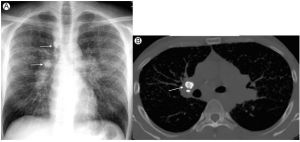

肺結節病

肺結節病曾被稱為肉樣瘤,是原因不明的變態反應疾病。肺結節病是一種非千略樣壞死的上皮肉芽腫病變。肺結節病較肺痛發病年齡輕。肺內結節病的分型:無異常X線所見...